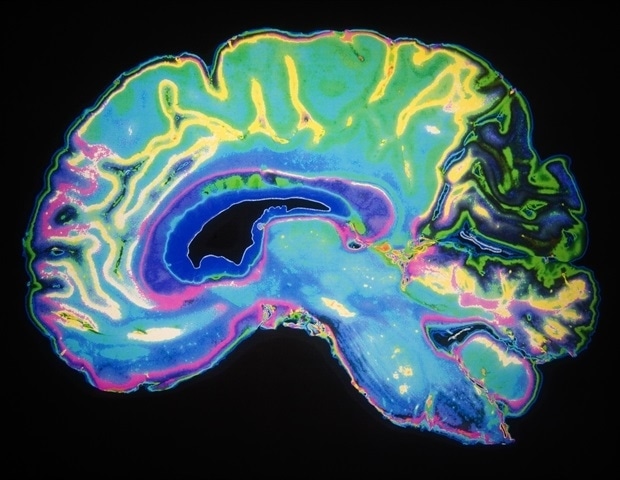

Известно, что черепно-мозговые травмы значительно повышают риск развития болезни Альцгеймера и других нейродегенеративных заболеваний, но ученые плохо понимают, почему. Новое исследование Люкенса предполагает, что такие травмы нарушают функцию лимфатических сосудов, которые соединяют мозг и иммунную систему. Считалось, что эти сосуды, расположенные в защитных мембранах мозга (или «оболочках»), не существуют до тех пор, пока они не были обнаружены нейробиологами UVA в 2015 году. Теперь известно, что сосуды играют жизненно важную роль в очистке и защите мозга.